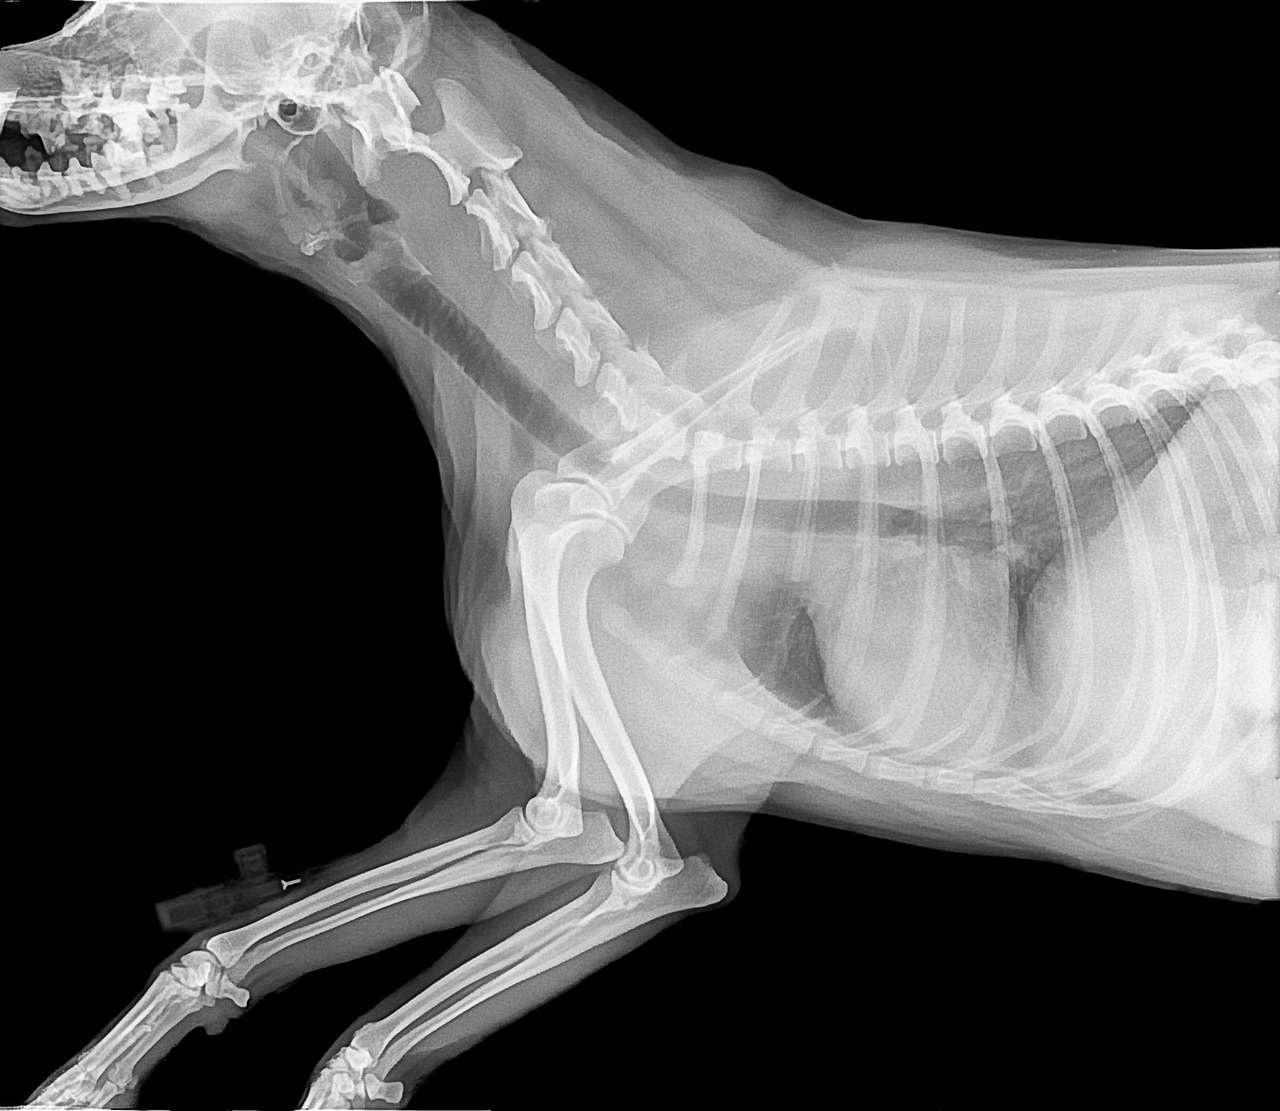

Radiographie

Pour assurer des diagnostics rapides et précis, notre clinique est équipée d’un plateau technique dédié aux examens complémentaires de vos compagnons à quatre pattes. Notre espace d’imagerie est doté de matériel performant, comprenant une radiographie numérique.

La radiographie permet quant à elle de diagnostiquer rapidement les pathologies osseuses, articulaires ou thoraciques, offrant ainsi une vue complète sur l’état de santé de votre animal.